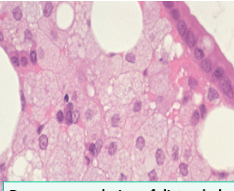

What are 2 things that should be in your diffential in this small intestine biopsy showing PAS positivity?

Whipple disease: Tropheryma whippelii

Mycobacterium Avium Complex (MAC): M. avium, M. intracellulare

What histologic appearance is seen in this small intestine biopsy?

Foamy macrophages - could be Whipple’s disease or Mycobacteria

What is the key to differentiating Whipple’s disease from MAC?

AFB positivity in MAC